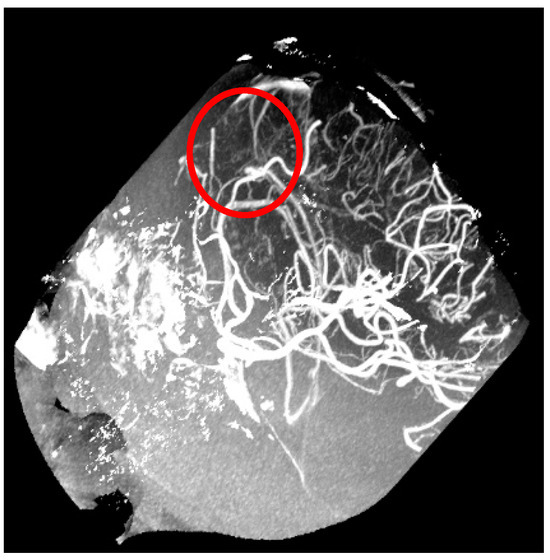

- Aziz, A.A.; Izhar, L.I.; Asirvadam, V.S.; Tang, T.B.; Ajam, A.; Omar, Z.; Muda, S. Detection of Collaterals from Cone-Beam CT Images in Stroke. Sensors 2021, 21, 8099. [Google Scholar] [CrossRef]